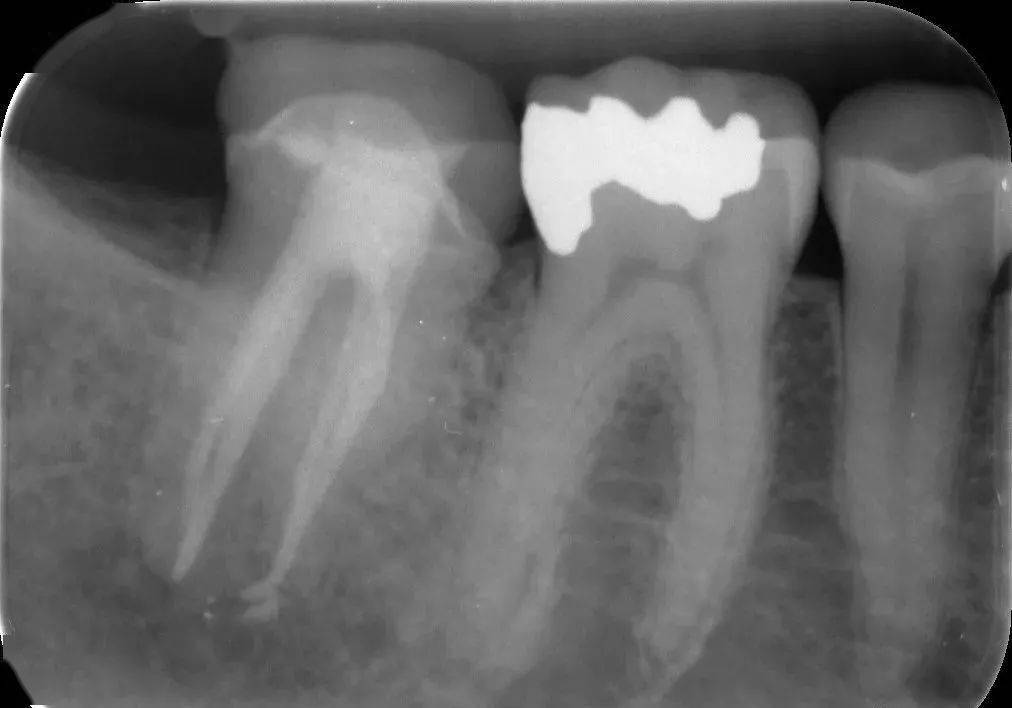

治疗计划:37,36根管治疗术.诊断:37牙髓炎,36根尖周炎.

图片尺寸934x676